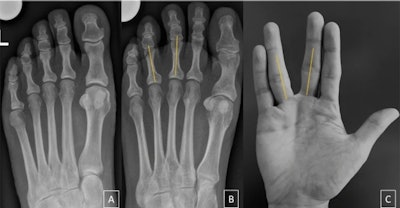

Morton's neuroma can lead to a divergence of the toes, which looks like the Vulcan salute on x-ray, according to the authors.

For those unfamiliar with the "Star Trek" television series and the Mr. Spock character, the Vulcan salute (shortened to "V-sign" in the article) is a hand gesture made by parting the middle and ring fingers while the palm is facing forward and the thumb is extended.

The researchers found a significant difference between the groups regarding the presence of the V-sign, which was found in 30 of 100 patients in the Morton's neuroma group and in three of 100 control patients, with a sensitivity of 30% and a specificity of 97%.